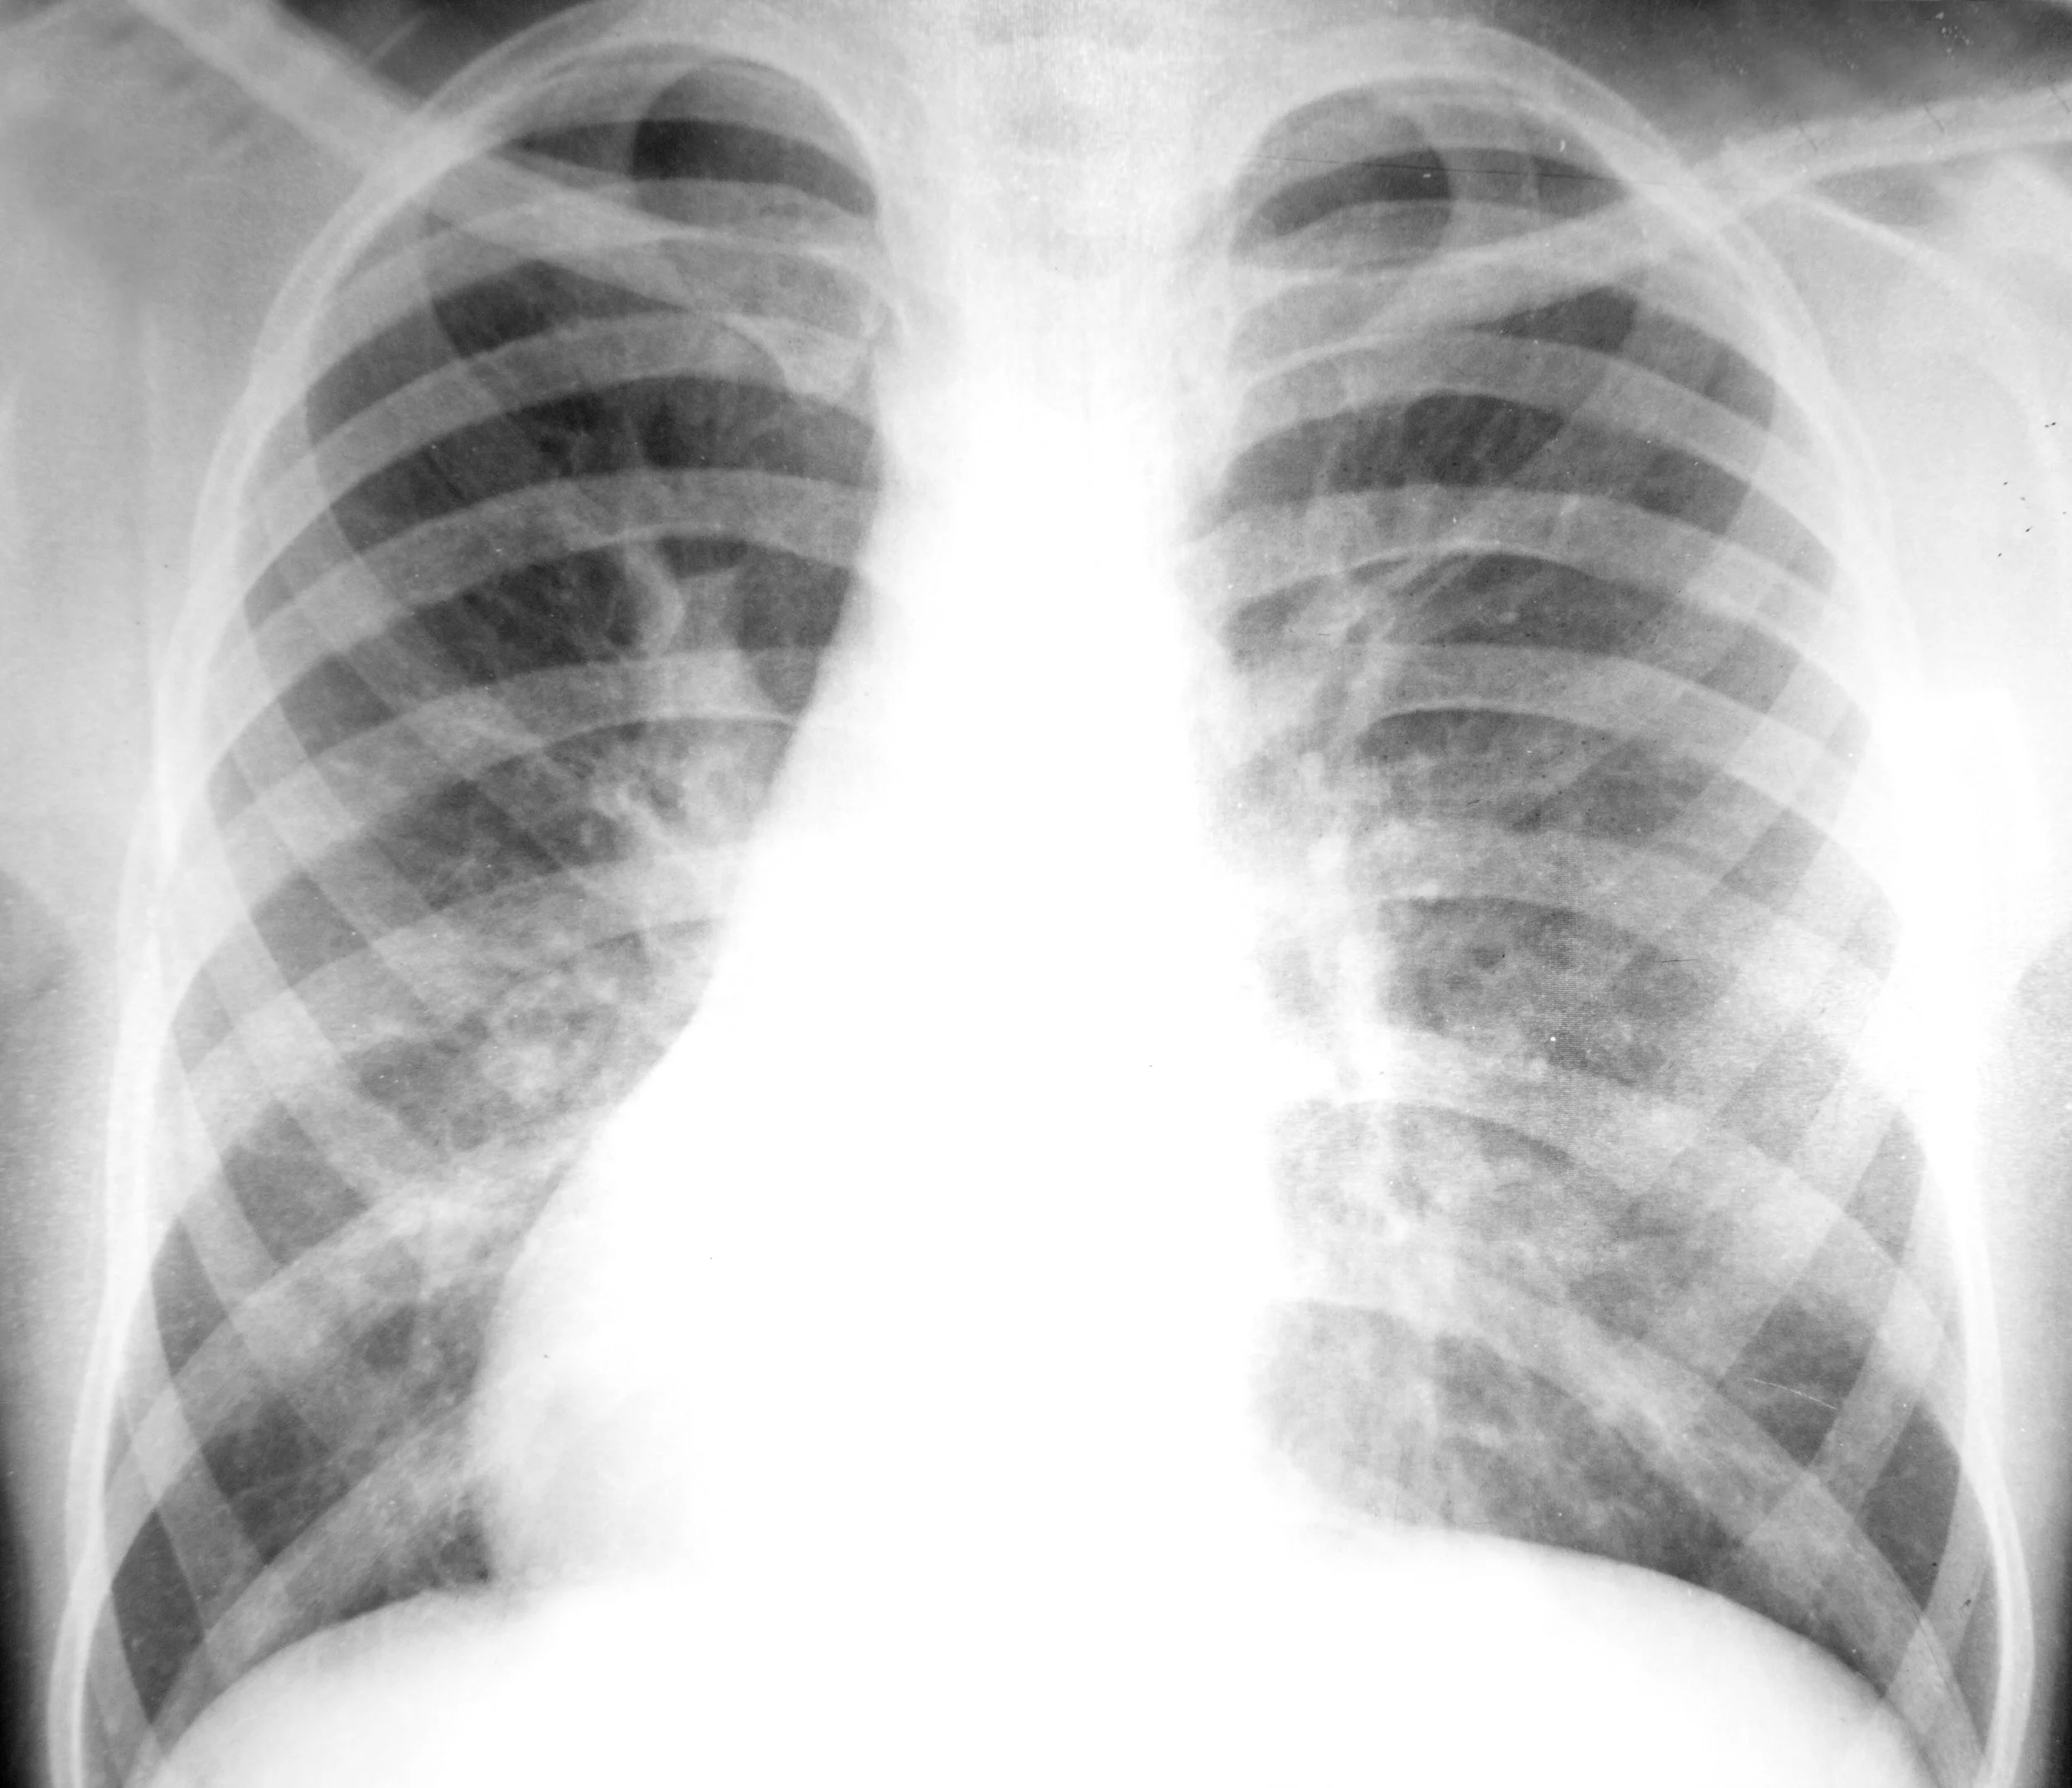

Rib fracture